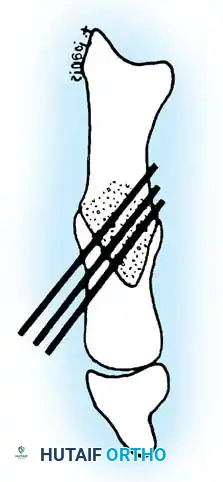

• Grasp the hallux in one hand and displace the proximal remnant medially so that, under direct vision, two longitudinal 0.062-inch Kirschner wires can be inserted.

• Hold the interphalangeal joint straight while drilling the wires from proximal to distal, emerging a few millimeters plantar to the nail plate.

• Return the foot to the corrected position, and drill the wires into the metatarsal head.

• While holding the metatarsal as far laterally as possible, cross the joint, and drive the wires out the plantar cortex just proximal to the head, while holding the hallux in 10 to 15 degrees of extension, neutral abduction, adduction, and rotation, and no translation dorsally or plantarward on the metatarsal head. The wires should penetrate only 2 to 3 mm past the cortex to avoid tenderness over the wires with weight bearing.

• If the Kirschner wires tend to “walk” on the rounded articular surface of the metatarsal head, use a small hemostat snugged up against the wire while it is being drilled to allow accurate placement. Proper placement of the wires and the desired position of the hallux on the metatarsal may require several attempts. The medial aspect of the proximal phalanx should not rest medial to the medial aspect of the metatarsal head.

• Place the hallux in the neutral medial-lateral plane and in 10 degrees of extension.

• Before the second wire is driven into the fi rst metatarsal head, place the hallux in proper rotation, using the plane of the nail as a guide. The initial length of the hallux is maintained by the wires. Later, collapse occurs when the wires are removed, but improved encapsulation of the hemiarthroplasty, by maintaining length for the fi rst few weeks, may help maintain a more desirable position long-term.

• Cut the wires off 2 to 3 mm distal to the skin edge.

• When the sesamoid has been removed, insert two 0.062-inch Kirschner wires retrograde from the tip of the toe 2 to 3 mm plantar to the nail bed, leaving about 5 to 7 mm of the pins exposed at the base of the phalangeal remnant to help align the phalanx on the metatarsal before antegrade passage of the pins into the metatarsal (Fig. 78-31F).